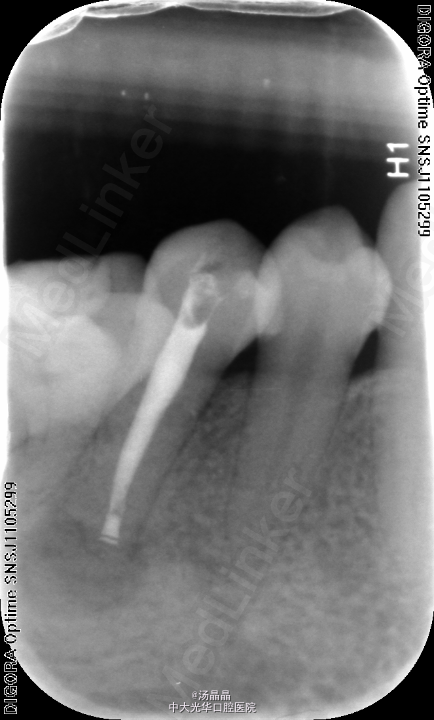

45咬合面探及深在龋损,叩(+—)松(-),X线:45根尖阴影,根尖孔闭合不全

45根尖周炎,去腐,探及一根管,疏通,预备后,封Vitapex,GIC暂封

3月复查,根尖阴影明显消失,换药,继续随访